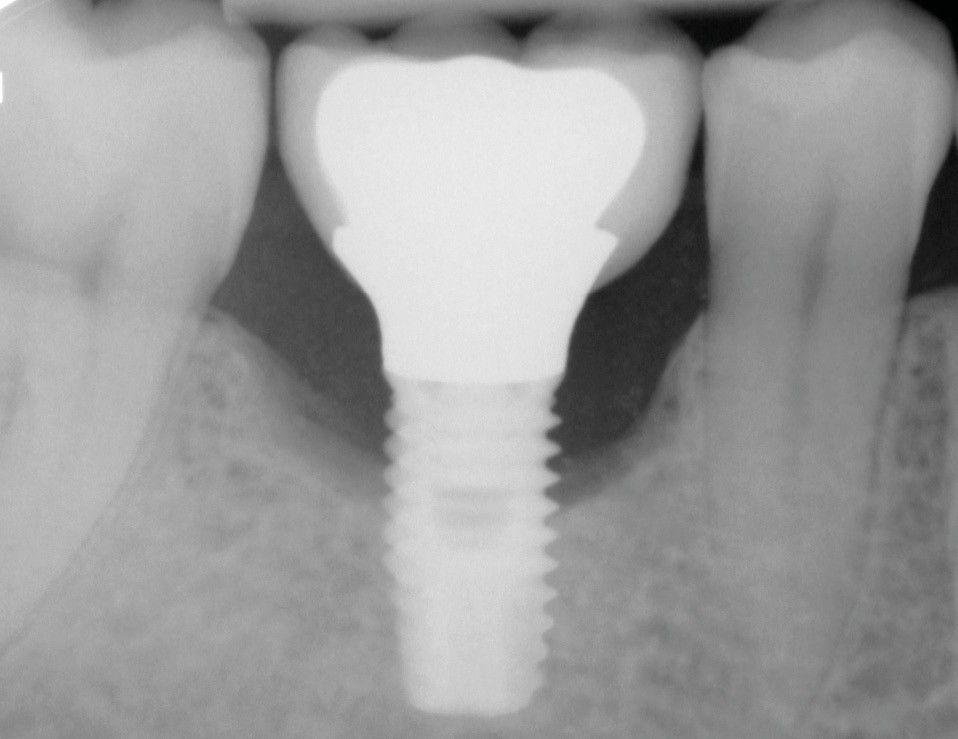

Les critères qui permettent de diagnostiquer une péri-implantite sont aujourd’hui bien établis, les voici rappelés : signes cliniques d’une inflammation péri-implantaire (gonflement, rougeur, saignement au sondage et/ou suppuration) (fig. 1a), perte osseuse péri-implantaire au-delà de celle constatée après la cicatrisation « initiale » (fig. 1b), augmentation de la profondeur de poche au sondage en comparaison de la profondeur de poche identifiée lors de la mise en place de la restauration prothétique [2, 23]. En l’absence de documents radiographiques préexistants, une perte osseuse supérieure ou égale à 3 mm en association avec un saignement au sondage et une profondeur de poche au sondage supérieure ou égale à 6 mm permet également de poser le diagnostic de péri-implantite [23].